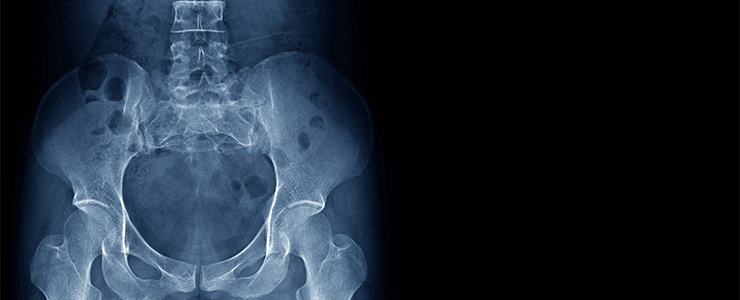

骨盤は内臓のゆりかご……レントゲン検査だけではダメな理由

頭骨や骨盤は特に重要な役割を担っており、例えば頭骨が歪めば脳や神経に重大な異常が発生するでしょう。また、骨盤が歪めば循環器系や神経系をはじめとした多くの器官に支障をきたすようになるはずです。

骨盤はいわば内臓のゆりかご。しかし、それほど重要なパーツであるにも関わらず、健康状態を確認するための検査では邪魔者扱いされてしまうケースがあります。

骨格に隠された部位を写せないという性質です。そのため、骨盤に隠された臓器や血管の状態を確認するには別の手段を取らなければなりません。